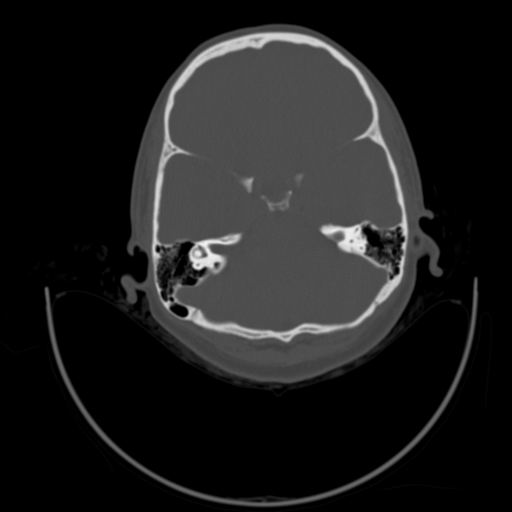

以下是引用随光逐影在2009-3-14 7:58:00的发言:[br]双耳——颞骨ct轴位平扫未见明确异常。